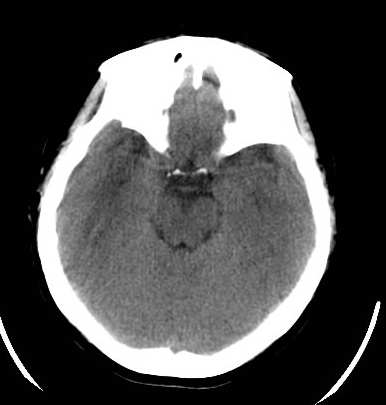

脑外伤患者,无外伤性改变

平均ct值 -60hu

小乔(楼主)说:平均ct值—60hu。考虑脂肪瘤。

颅内脂肪瘤系因隶属于中胚层的脂肪掺合进正在关闭的神经管之中,绝大多数见于胼胝体膝部,肿瘤较小;偶尔可发生在整个胼胝体,肿瘤较大。颅内脂肪瘤也可见于四叠体池,鞍上池,大脑脚池以及桥小脑角池。约有50%的中线脂肪瘤并有胼胝体发育不全,但是,胼胝体发育不全很少并有脂肪瘤。胼胝体脂肪瘤有症状的仅占一半,主要为癫痫,痴呆,头痛,半身不遂。癫痫系因脂肪瘤使邻近的纤维性结缔组织浸润到周围脑组织所致。脂肪瘤占位效应不明显,由于它浸润性生长,有时可造成对邻近血管如大脑前动脉的包绕,可影响正常脑脊液通路而导致脑积水。

既然ct值为-60hu,当然首先考虑脂肪瘤,除此之外,我们还应该注意四脑室改变,建议增强扫描

颅内脂肪瘤少见,占颅内肿瘤的1%以下。有人认为不是肿瘤,而是原始脑膜组织的畸形。好发于胼胝体及其周围。胼胝体区脂肪瘤多并发于胼胝体发育不良。瘤体呈圆形或分叶状,大小不等,境界清楚。ct上,病灶呈脂肪密度的圆形或分叶状肿块,周边可见弧形钙斑。无瘤周水肿。无强化。本例发生于胼胝体区低密度肿块,ct值-60,应是典型的胼胝体区脂肪瘤。